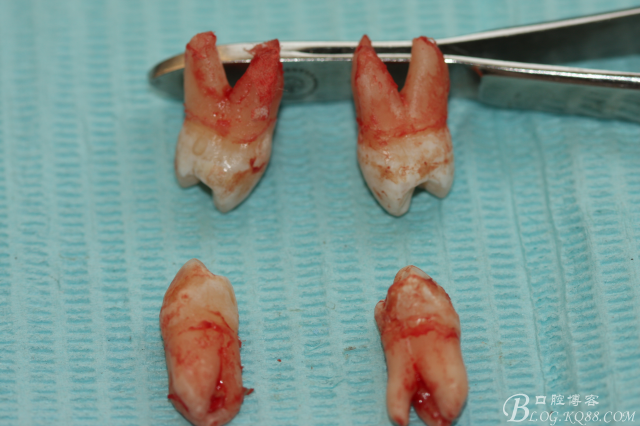

4.術(shù)中拔除下頜第一前磨牙照片

6.下頜離體第一前磨牙牙根形態(tài)